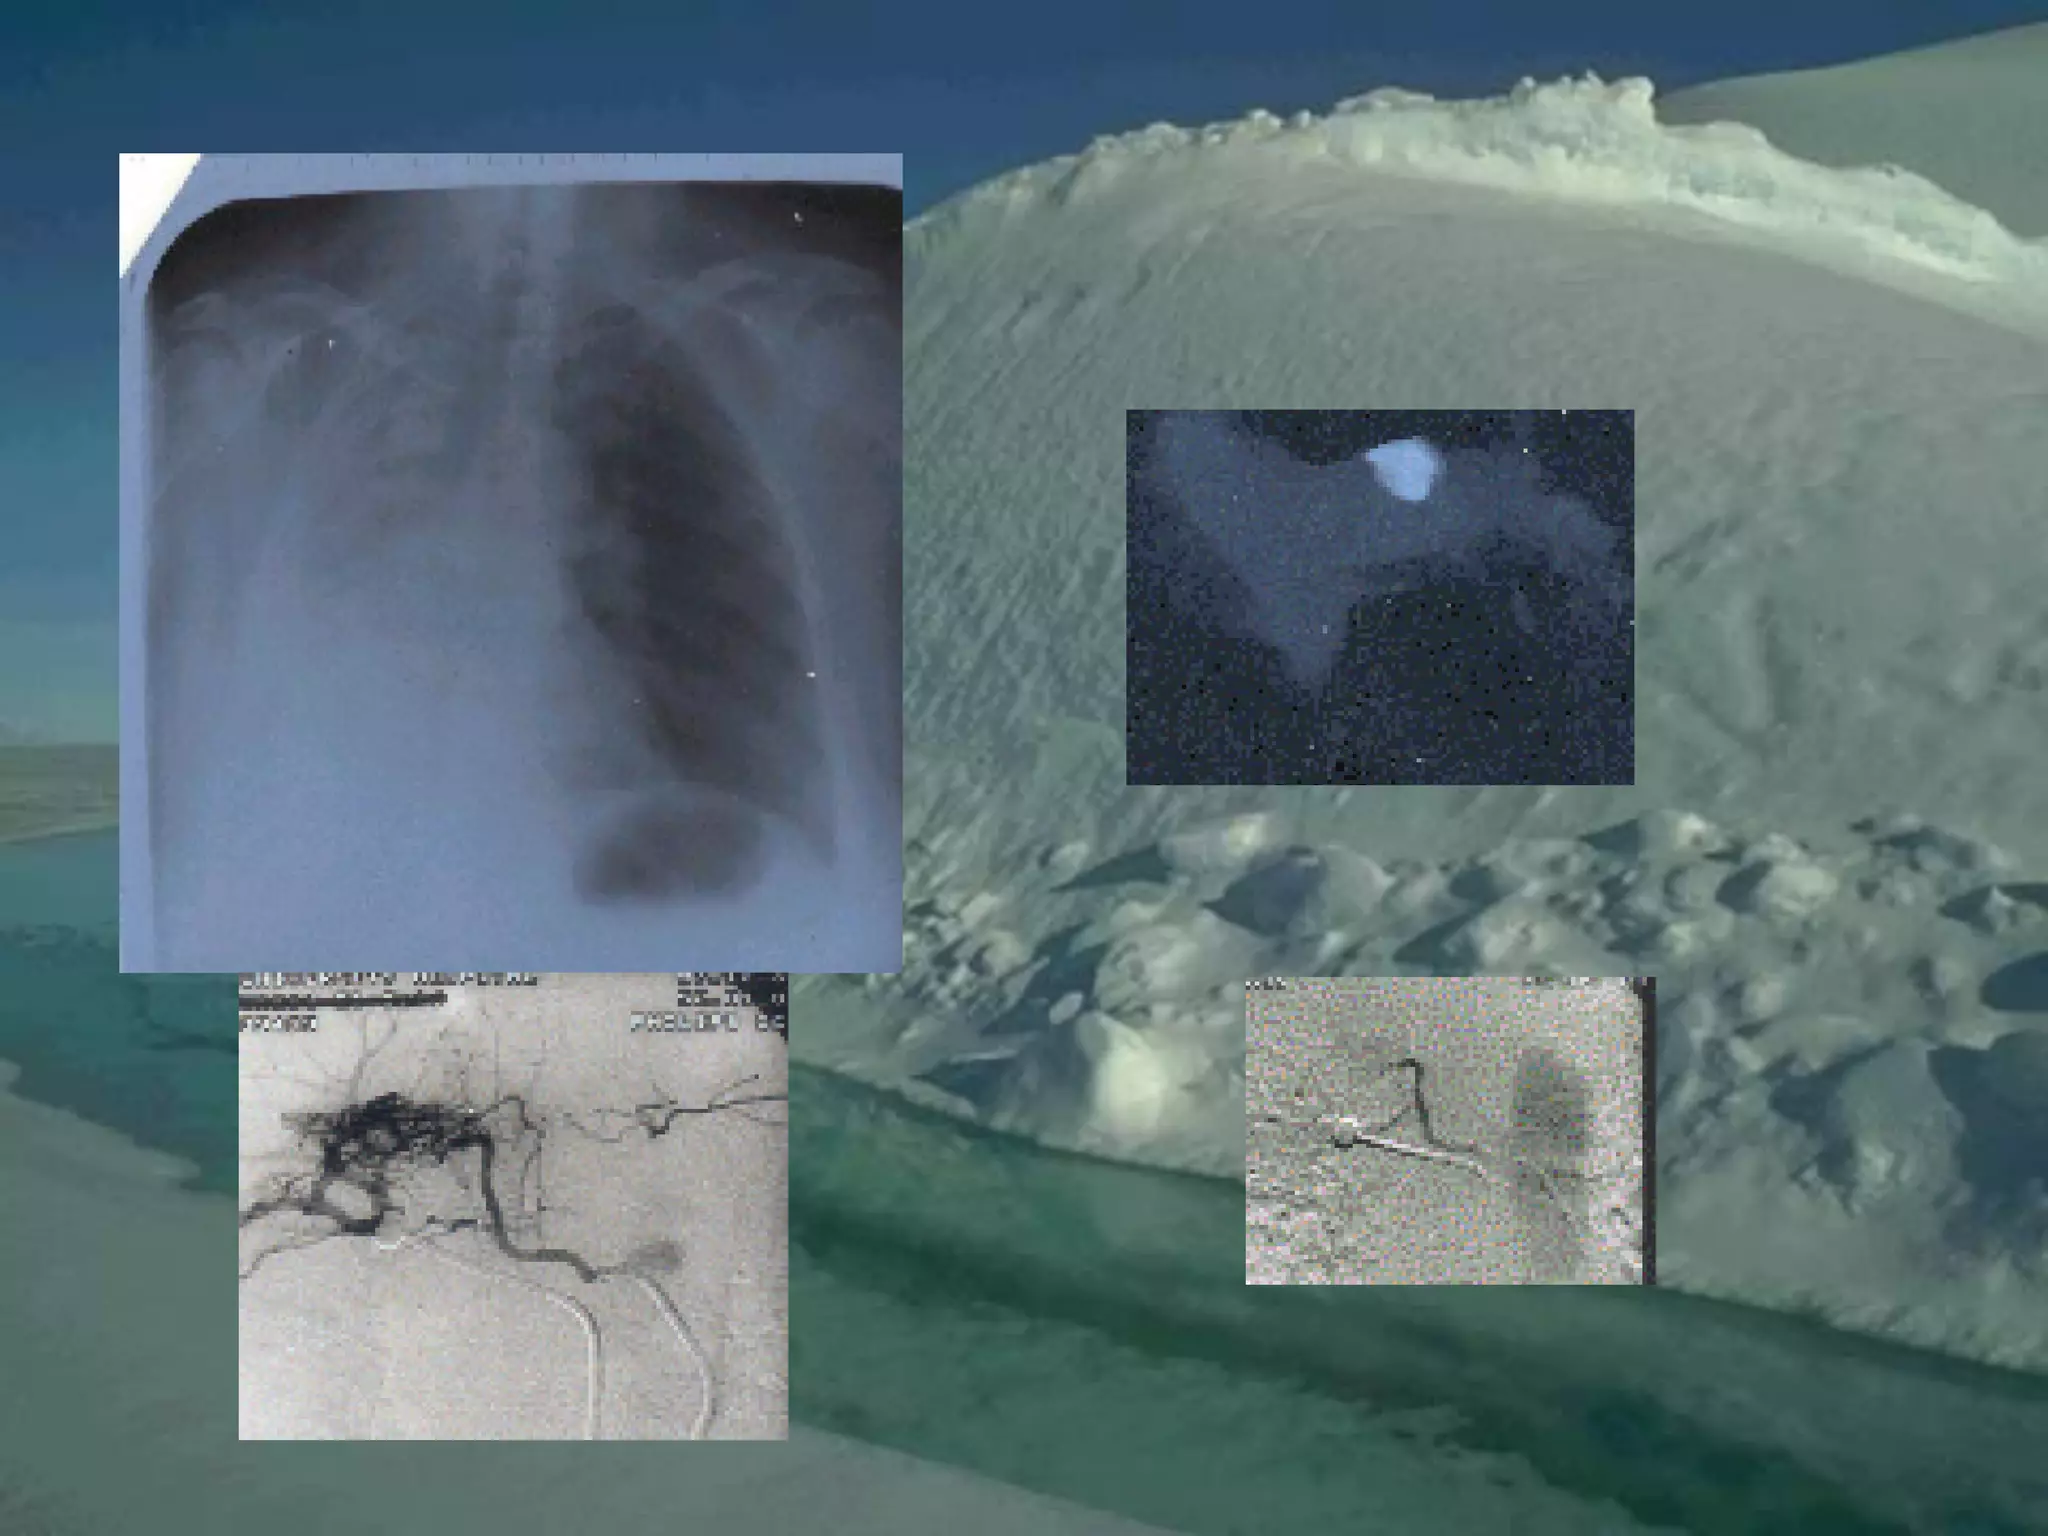

CT Scan and MRI Scan in the

diagnosis of TB

􀂄 The advent of CT and MRI imaging in

the last two

decades has redefined the approach in

analysis of

various diseases including TB.*

􀂄 CT and MRI have shown several

advantages over

conventional radiology in early diagnosis

and follow-up

of TB in different parts of the body.

*Buxi TBS Indian J Pediatr 2002;69:965-972

Pulmonary TB :

Lobar Pneumonia

􀂄

CT is superior than plain CXR in picking

up the

consolidation, atelectasis and the hilar LN

thereby

making the diagnosis easy.

􀂄 MRI reveals some of these changes,

however, CT is

the diagnostic modality of choice in such

cases.

Bronchopneumonia

On CT it is usually B/L and widespread,

not always

symmetrical involvement of lungs.

Hilar and Mediastinal

Lymphadenopathy

CT and MRI depict the hilar and

mediastinal LN

equally well.

􀂄 Calcification in the nodes is however

better seen on

CT.

􀂄 Necrosis is seen as focal areas of low

attenuation on

a CECT.

􀂄 On MRI focal necrosis is seen as areas

of increased

signal intensity on T2W images.

EBTB

HRCT is sensitive in the detection of

early

endobronchial spread of disease.

Miliary TB

􀂄 Earliest form of miliary TB is detectable

on HRCT.

􀂄 Coalescing nodules result into patchy

irregular

opacities and HRCT shows this variation

effectively

and has been described as “snowstorm

appearance”.

􀂄 HRCT shows cavitation, which is not

evident on plain

CXR.

Pleural Effusion 􀂄

􀂄 CT is sensitive to diagnose and define

even minimal

pleural effusion/pleural calcification.

􀂄 Pleural fluid is seen on inversion

recovery MR

images as areas of increased signal

intensity along

the inner aspects of the chest wall.